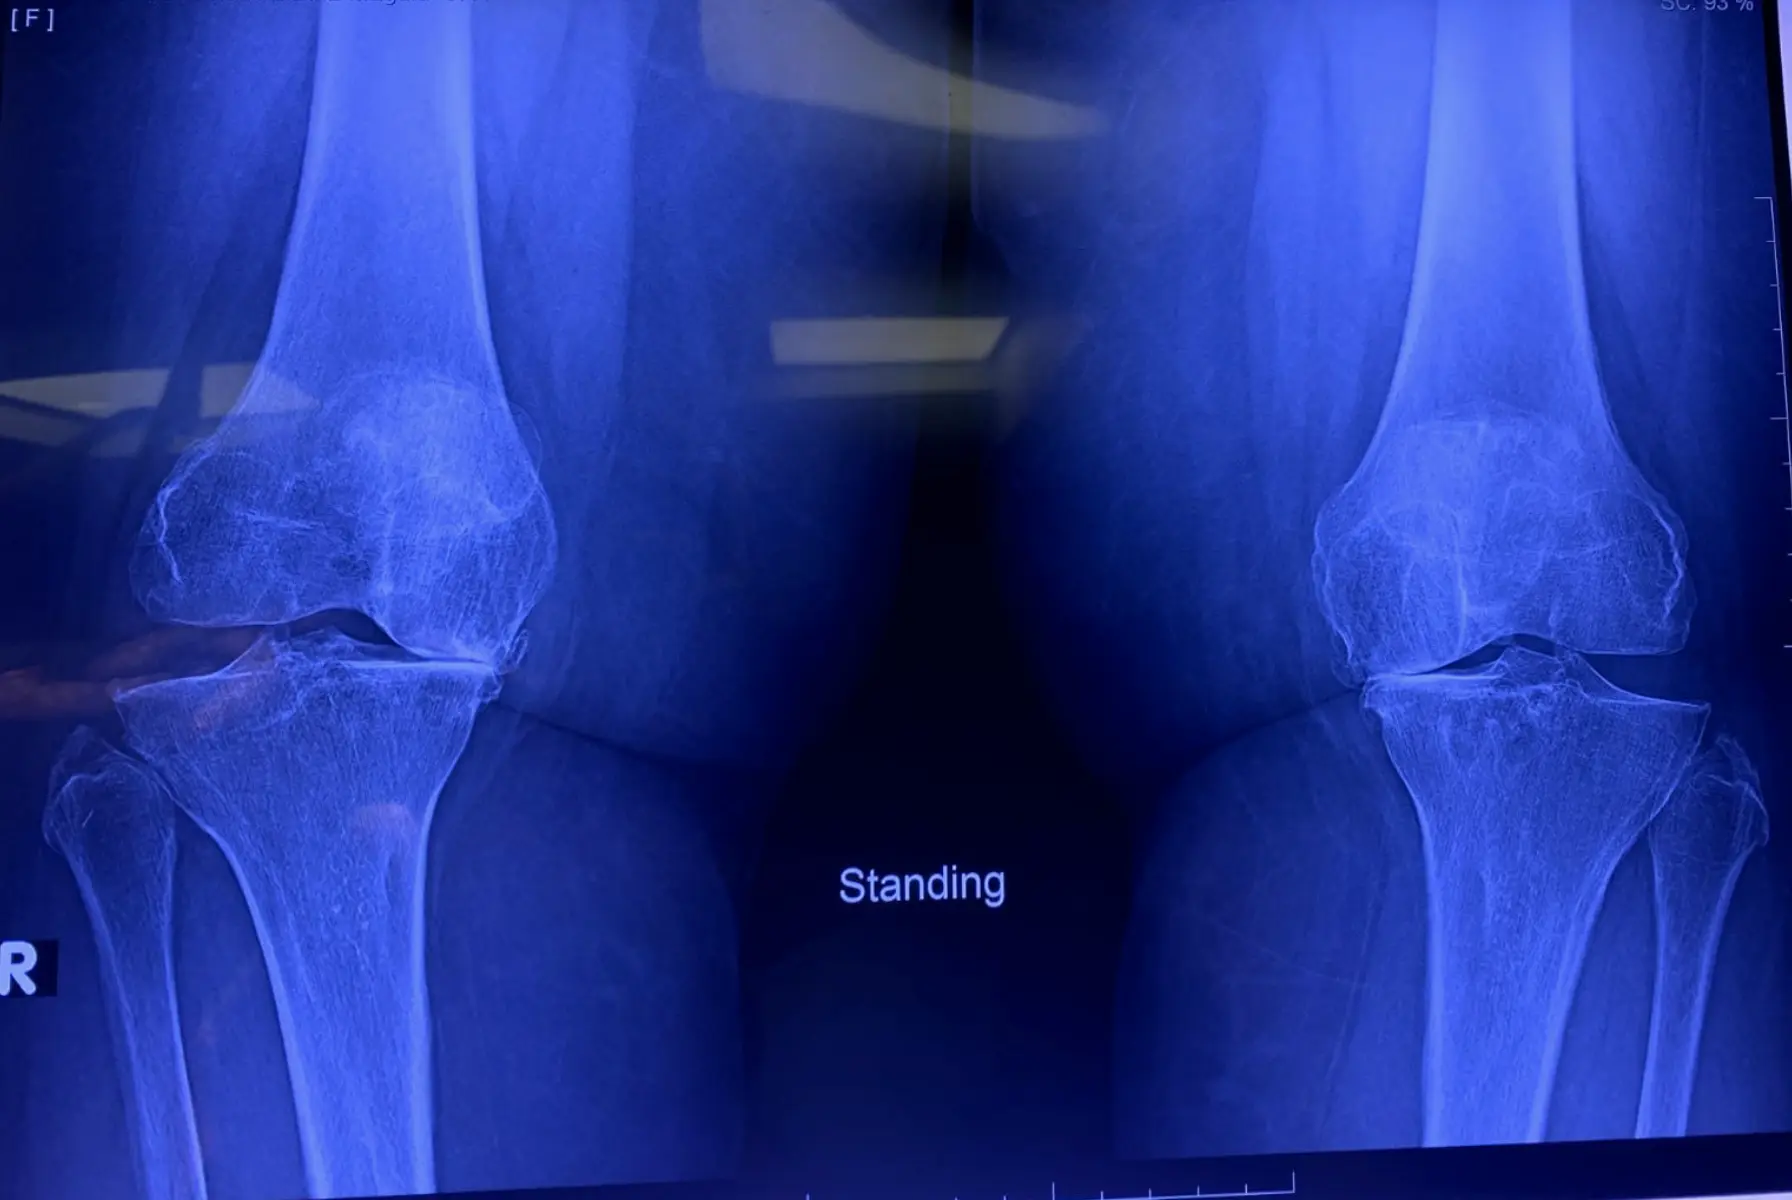

– الأشعة السينية. قد يقترح الطبيب أولاً إجراء أشعة سينية، والتي يمكن أن تساعد في اكتشاف كسور العظام وأمراض المفاصل التنكسية.

طرق التشخيص:

تشمل التقنيات التشخيصية الأشعة السينية والرنين المغناطيسي والفحص السريري. الاستشارة مع طبيب عظام متخصص ضرورية للتحقق من التشخيص.